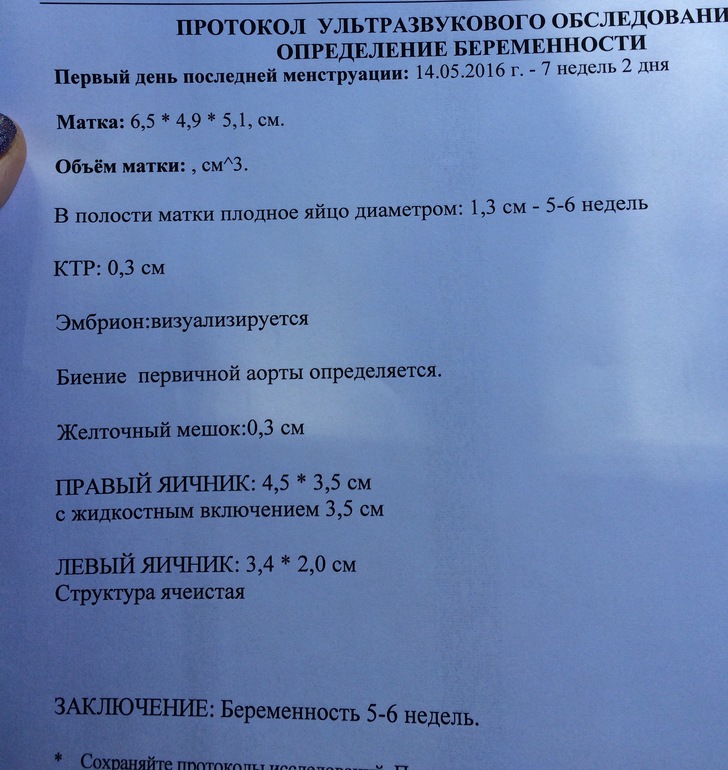

Фотографии на ранних этапах беременности

Раздел: Визуальный дайджест